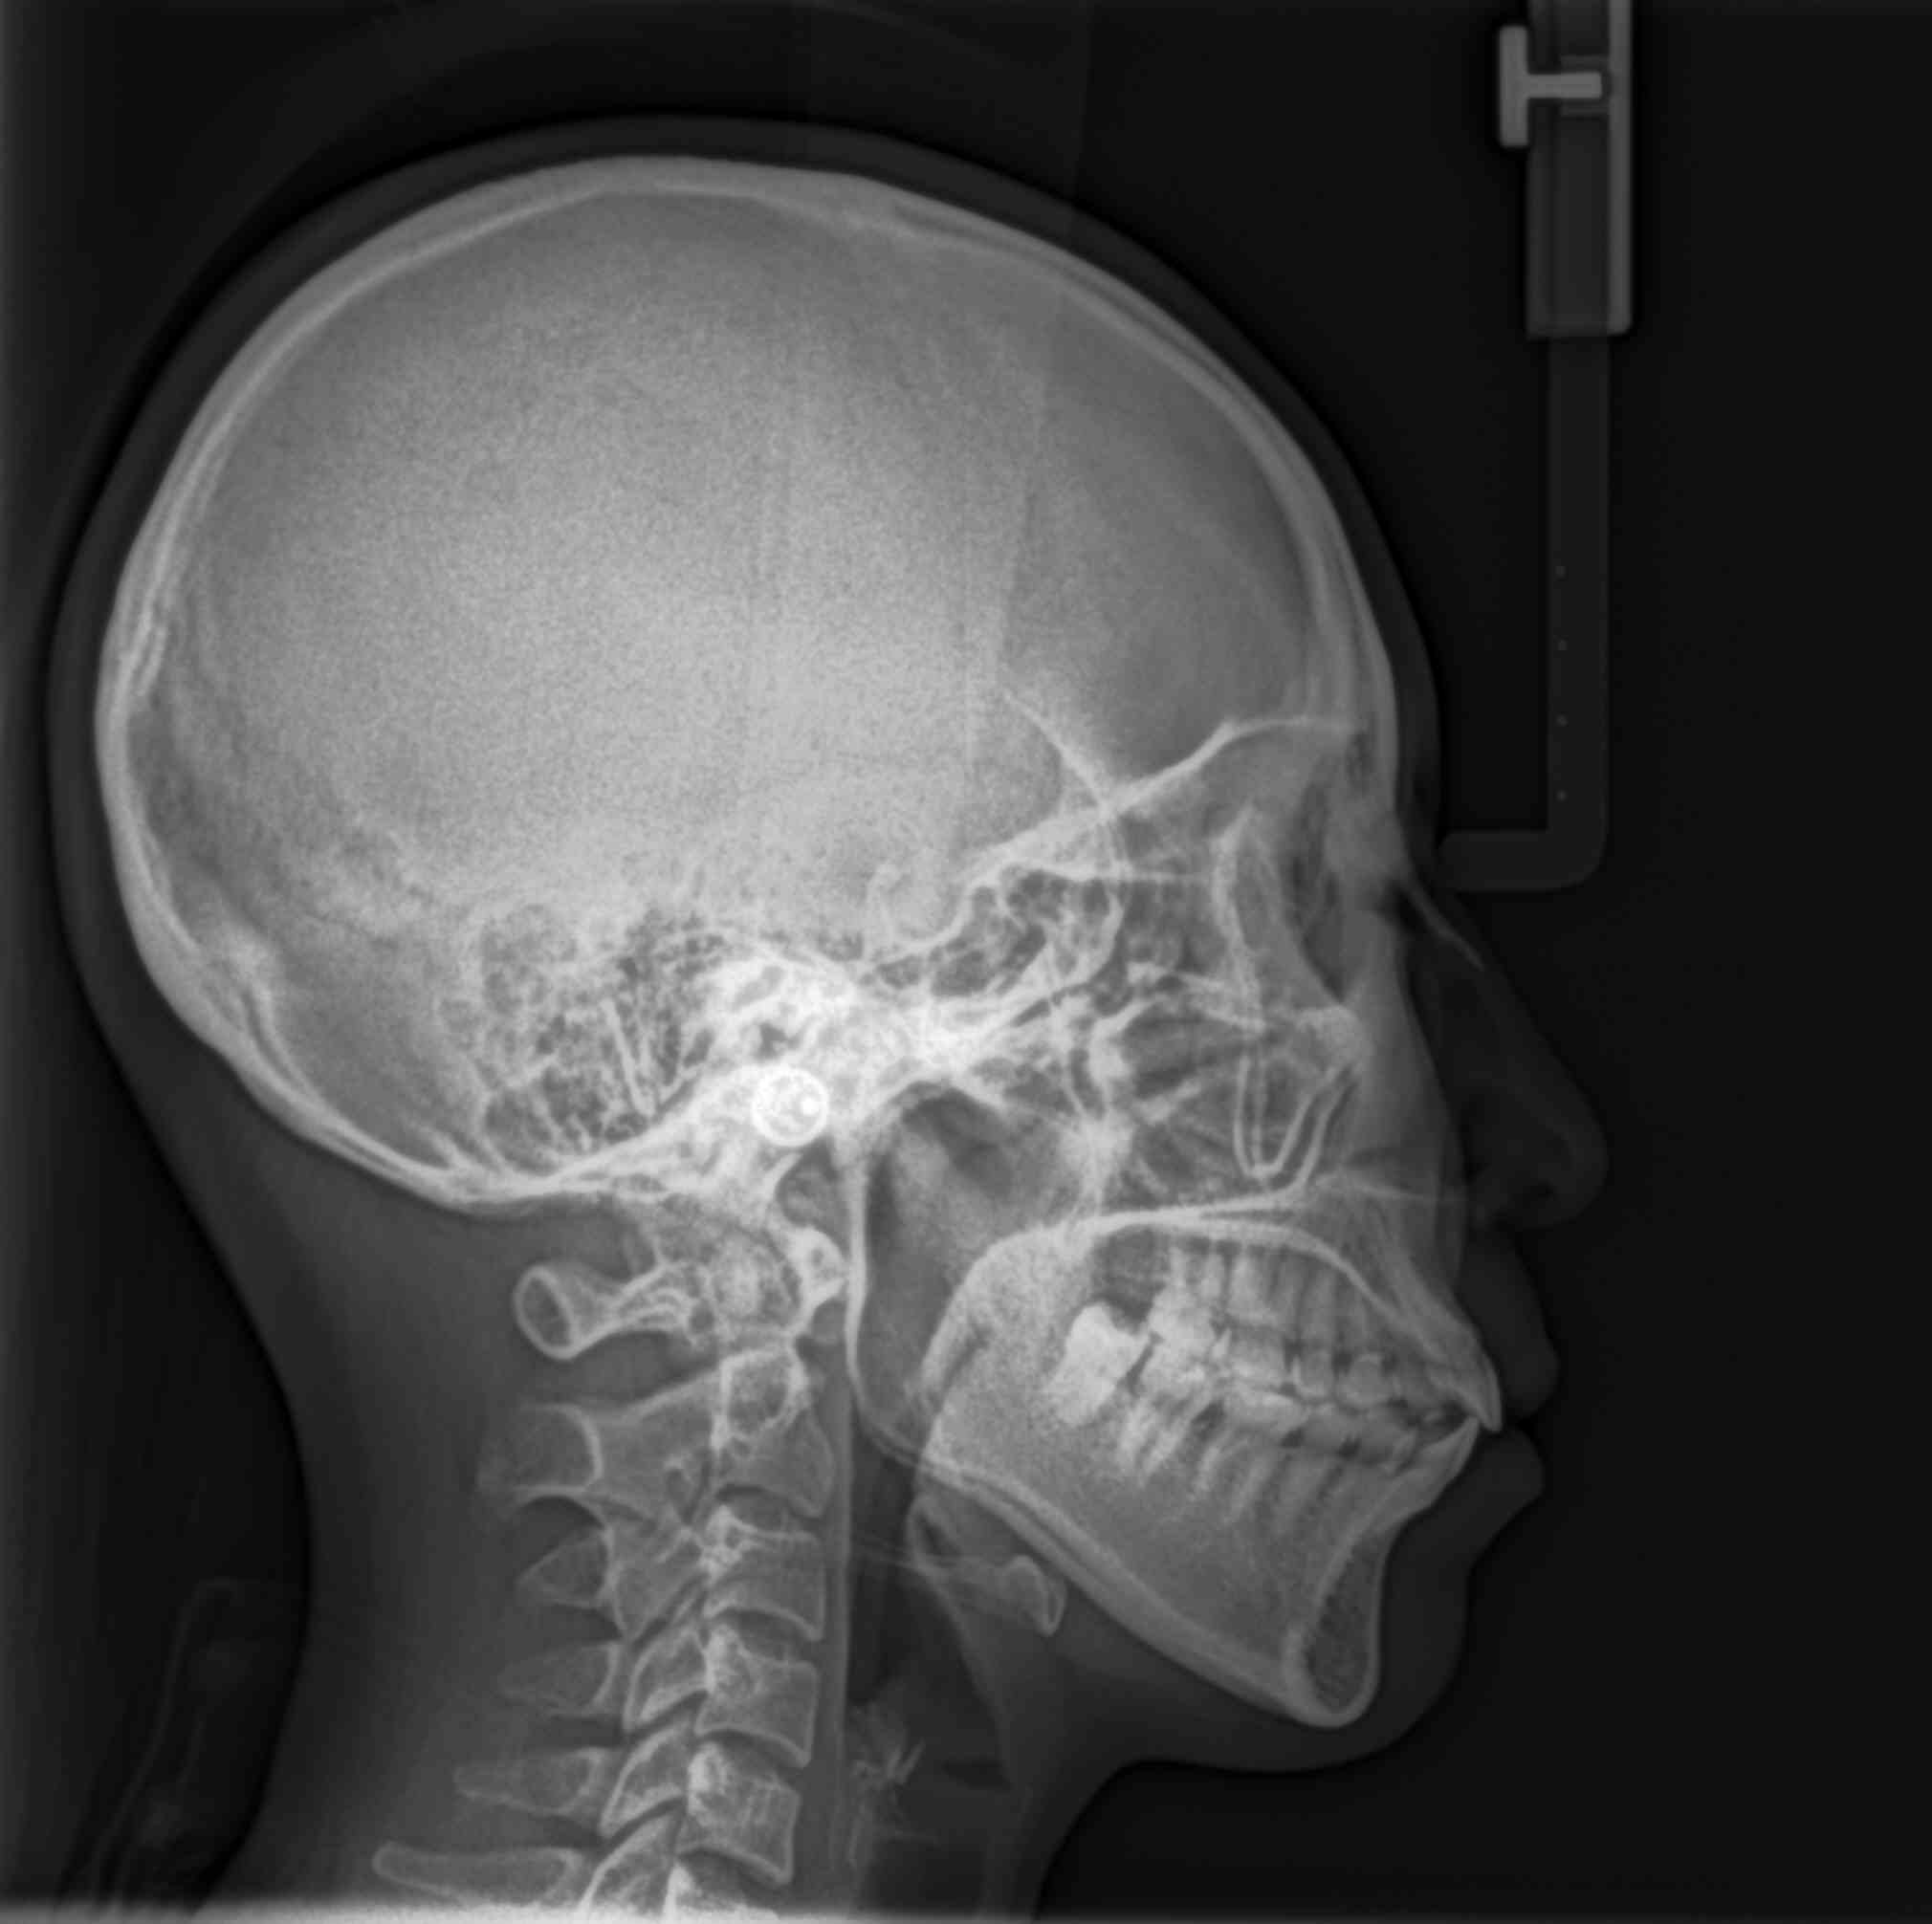

Carestream CS9000C Máy Chụp X-quang Nha Khoa Toàn Cảnh + Sọ Nghiêng Đã Qua Sử Dụng

Máy X-quang toàn cảnh + đầu dò sọ nghiêng đã qua sử dụng

Carestream CS9000C là hệ thống chụp ảnh toàn cảnh và sọ nghiêng kỹ thuật số hiệu suất cao đến từ thương hiệu Carestream Dental nổi tiếng toàn cầu. Được thiết kế để đáp ứng nhu cầu của nha khoa tổng quát và chỉnh nha, máy kết hợp hình ảnh kỹ thuật số rõ nét với công nghệ chụp sọ nghiêng one-shot — chụp toàn bộ hình ảnh chỉ trong một lần phơi sáng, mang lại kết quả nhanh chóng và ổn định.

✅ Công nghệ chụp sọ nghiêng one-shot: Khác với hệ thống quét truyền thống, phương pháp one-shot chụp toàn bộ hình sọ nghiêng trong một lần phơi sáng. Giảm nhiễu do chuyển động, rút ngắn thời gian chụp và đặc biệt phù hợp với trẻ em hoặc bệnh nhân lo lắng.

✅ Nhiều chế độ chụp Ceph: Hỗ trợ các góc chụp bên, PA/AP, chéo và các kiểu chụp chuẩn khác.